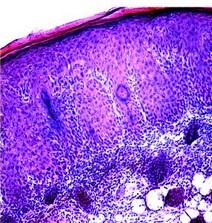

Øpour traiter le psoriasis : » dans le psoriasis « , souligne le Dr Marinkovich, auteur principal, » le ciblage d’une protéine dans la peau, plutôt que du système immunitaire, pourrait être une option avantageuse pour de nombreux patients et pour les cliniciens « . Ainsi, les chercheurs montrent que Rac1 est fortement activé dans les biopsies de la peau psoriasique de 20 patients atteints. De même, lorsqu’ils activent artificiellement Rac1 dans la peau de souris de laboratoire, les animaux présentent alors des symptômes similaires à ceux des patients humains (Visuels du haut).

Il apparaît possible de bloquer/réguler l’activité de la protéine : le blocage de l’activité de Rac1 dans des biopsies de peau humaine psoriasique greffées sur le dos des souris, inverse l’hyperplasie de la peau (cf vignette) et réduit le recrutement de molécules immunitaires appelées cytokines. Cibler l’activation de Rac1 dans la peau peut donc être un moyen de traiter le psoriasis, sans toucher au système immunitaire. La prochaine étape consistera à développer des médicaments topiques, sous forme de gel ou de pommade, capables de réguler à la baisse ou à la hausse l’activation de Rac1 anormale dans le psoriasis mais bienvenue dans la cicatrisation.